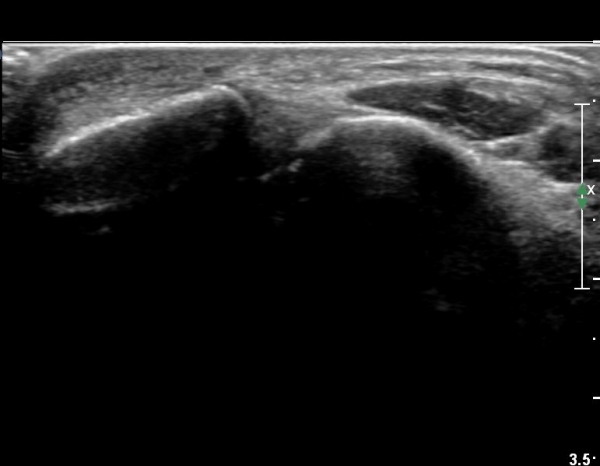

Àü¹æ¸»´ÜÁ¾°ñºñ°ñÀδë Á¾´Ü¸é°Ë»ç¿¡¼­ ƯÀÌ ¼Ò°ßÀ» º¸ÀÌÁö ¾ÊÀ½(»çÁø 1).